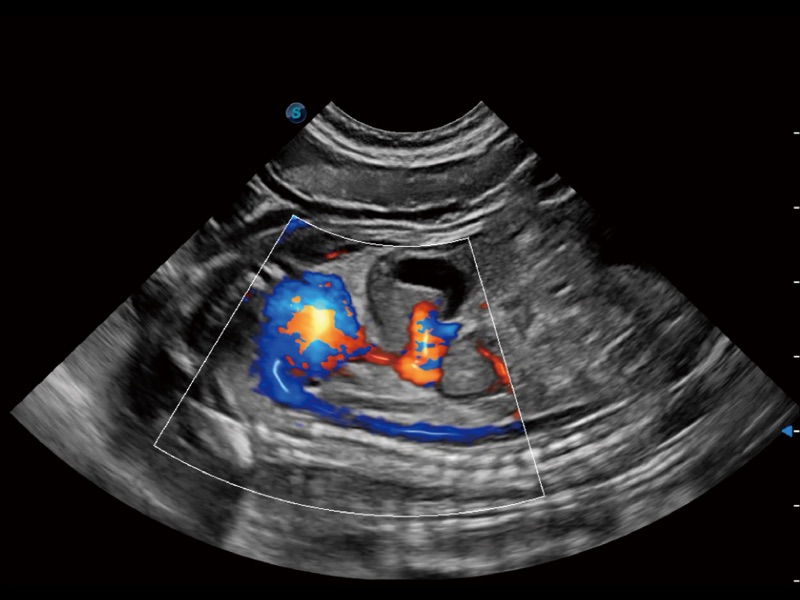

通过色彩血流和实时宽景相结合,可观察到完整的静脉或动脉的血流,方便医生检查。实时扫查过程中,如有任何操作失误也可以很容易地进行回扫擦除,而不会中断扫查。

通过360度任意调节3条M型取样线,在同一心动周期上观察心脏不同位置的运动曲线,得到准确的心功能测量数据,有效评估心肌运动及左心室功能。